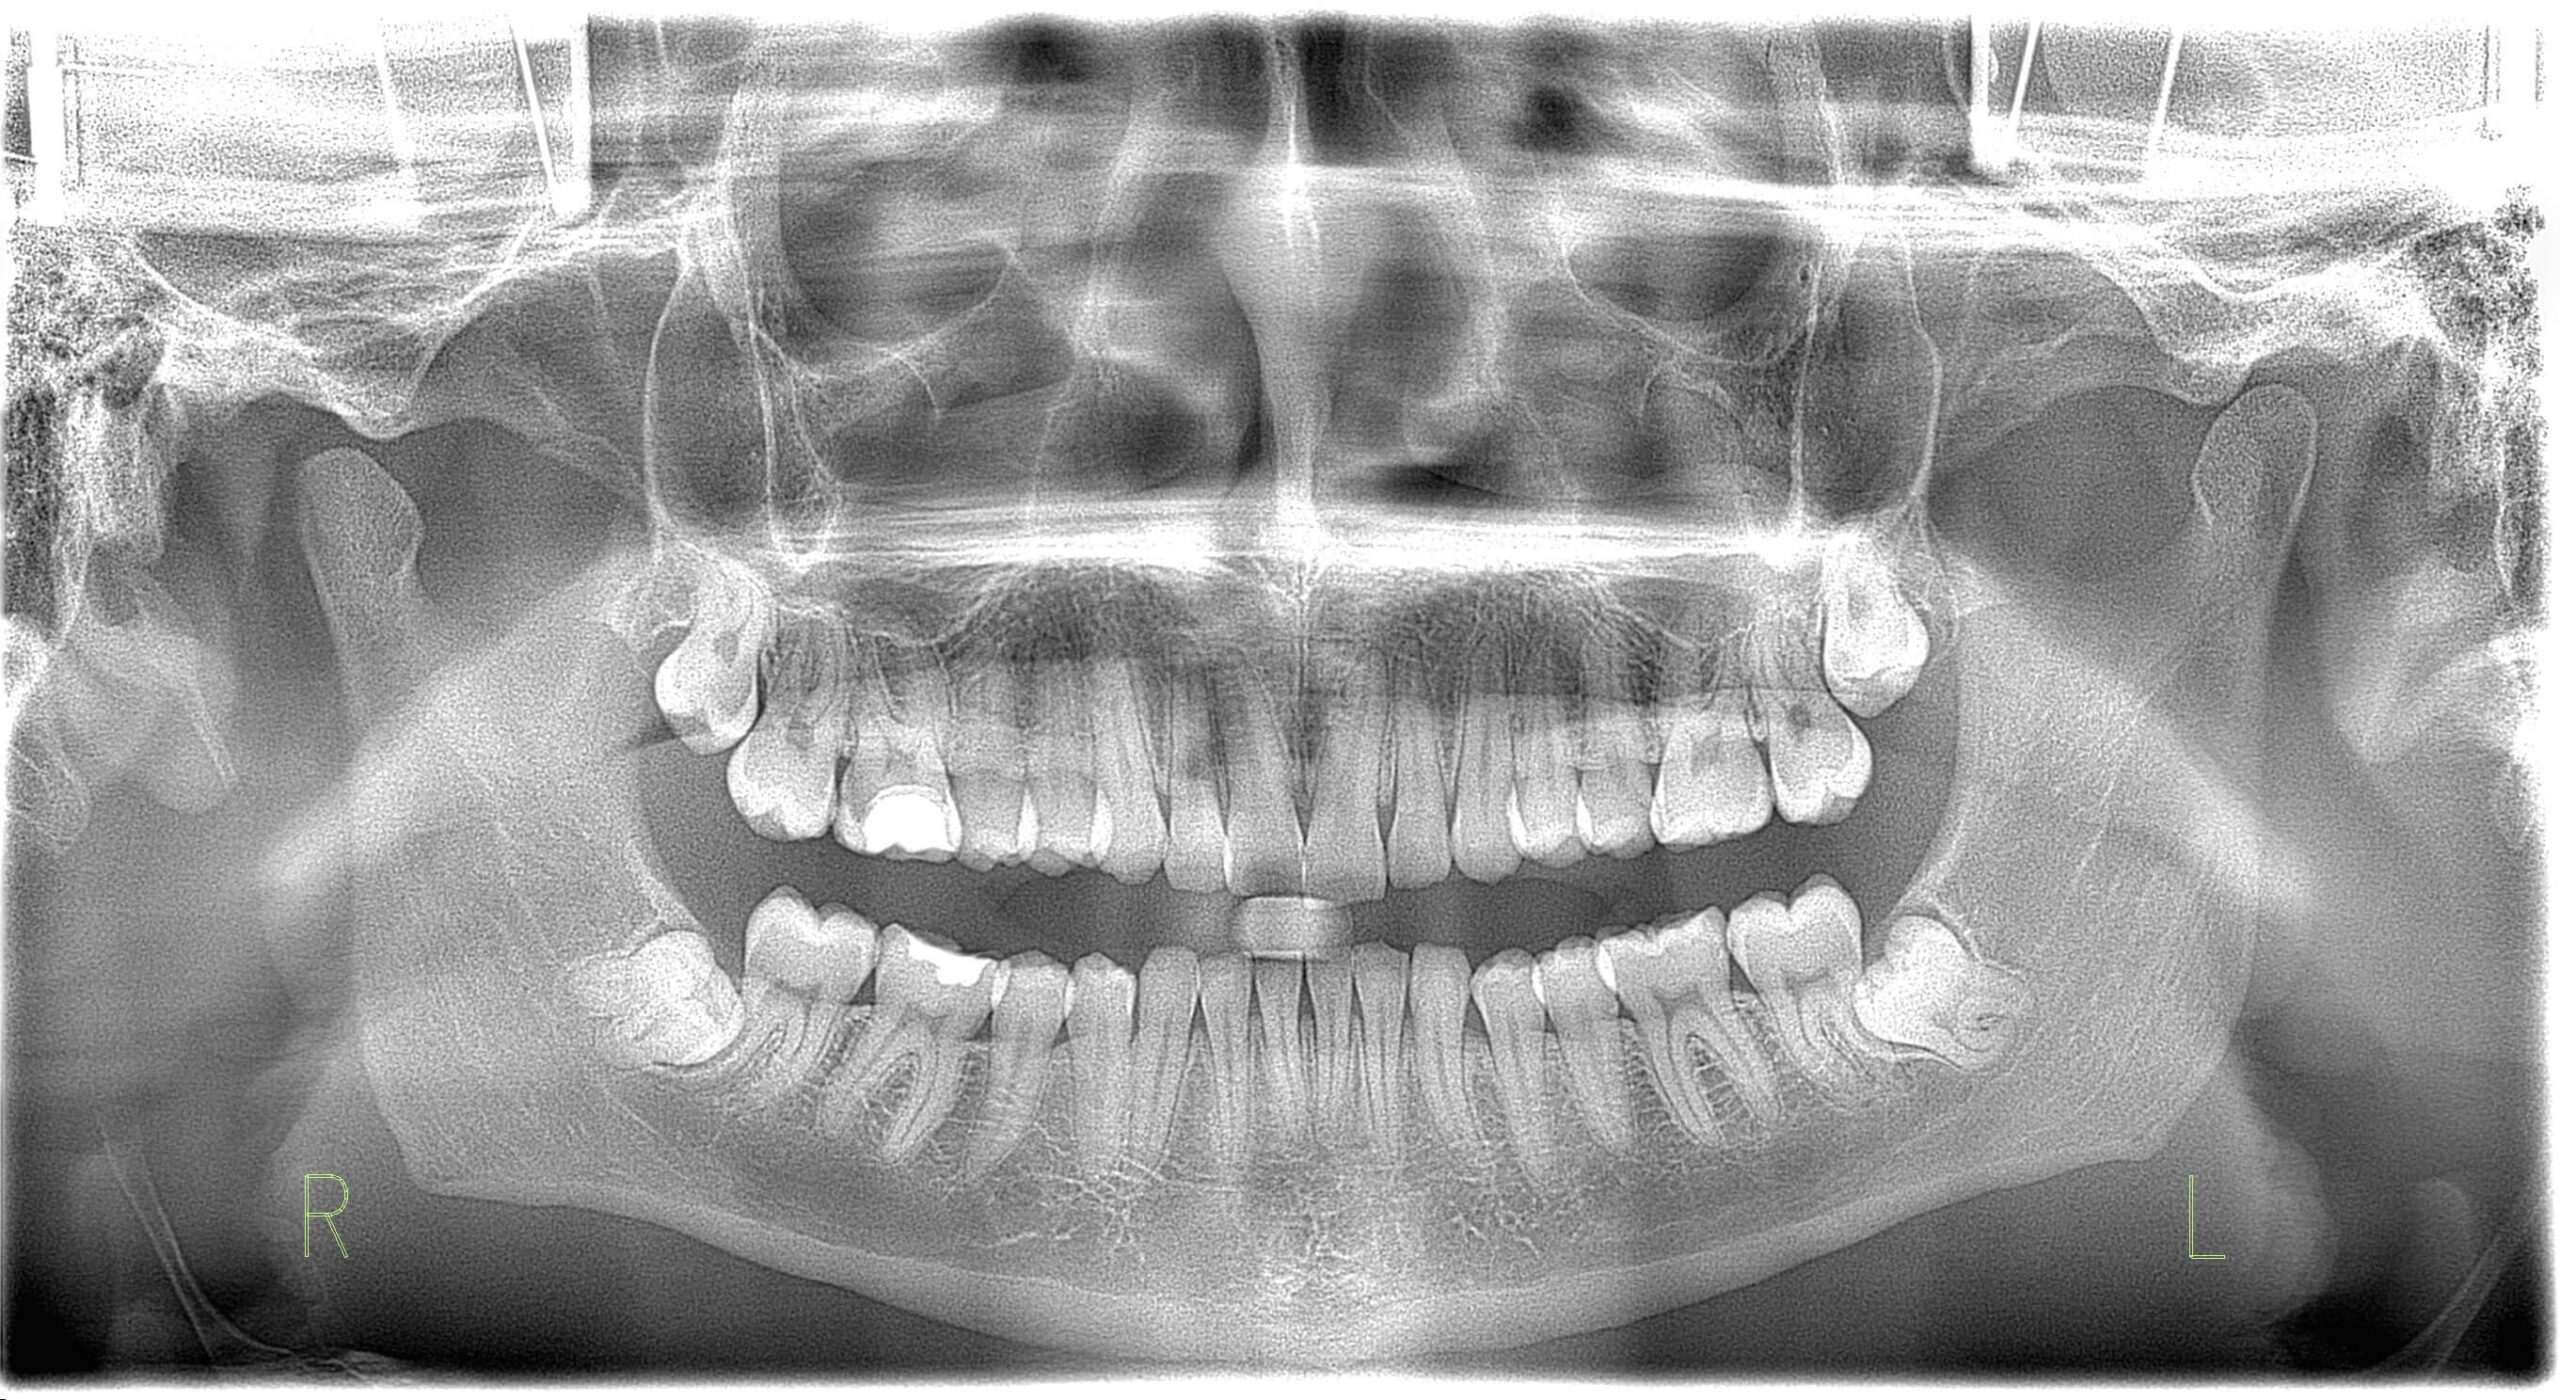

Molti pazienti si chiedono che cos’è l’ortopanoramica e a cosa serva durante la prima visita. L’ortopanoramica è una radiografia panoramica che mostra entrambe le arcate, tutti i denti, le loro radici e l’osso circostante. Mostra anche l’articolazione della mandibola e alcune parti dei seni paranasali che sono importanti per una diagnosi completa.

Il vantaggio principale dell’ortopanoramica è la sua eccezionale visione d’insieme. In un’unica immagine si possono individuare diversi potenziali problemi contemporaneamente. Questo non significa che sostituisca tutte le altre metodiche di imaging. Tuttavia, è spesso il primo passo più utile quando si pianifica un intervento più impegnativo.

A differenza delle piccole immagini di un singolo dente, l’ortopanoramica fornisce la “visione generale” e un quadro dei rapporti tra le strutture. Il dentista la usa per valutare le condizioni generali della bocca. Se si cerca la causa di sintomi poco chiari, questa radiografia è uno strumento irrinunciabile nell’odontoiatria moderna.

Molti problemi dentali all’inizio non presentano sintomi chiari e intensi. L’ortopanoramica può rivelare cambiamenti nascosti nell’osso e nelle aree intorno agli apici radicolari. Può mostrare anche radici residue e infiammazioni silenti che possono restare attive per anni senza dolore.

Nei bambini e negli adolescenti, l’ortopanoramica svolge un ruolo chiave nel monitorare lo sviluppo. Mostra i germi dei denti permanenti e la loro direzione di eruzione. In questo modo, i genitori possono scoprire per tempo se il bambino avrà bisogno di un supporto ortodontico.

È particolarmente importante per i denti del giudizio, che spesso restano inclusi nell’osso (denti inclusi). L’ortopanoramica mostra chiaramente il loro rapporto con i nervi e con i denti vicini. In base a questo si decide se eseguire un’estrazione preventiva o monitorare la crescita. Se è previsto un apparecchio fisso, insieme alla teleradiografia si analizza lo sviluppo craniofacciale complessivo.